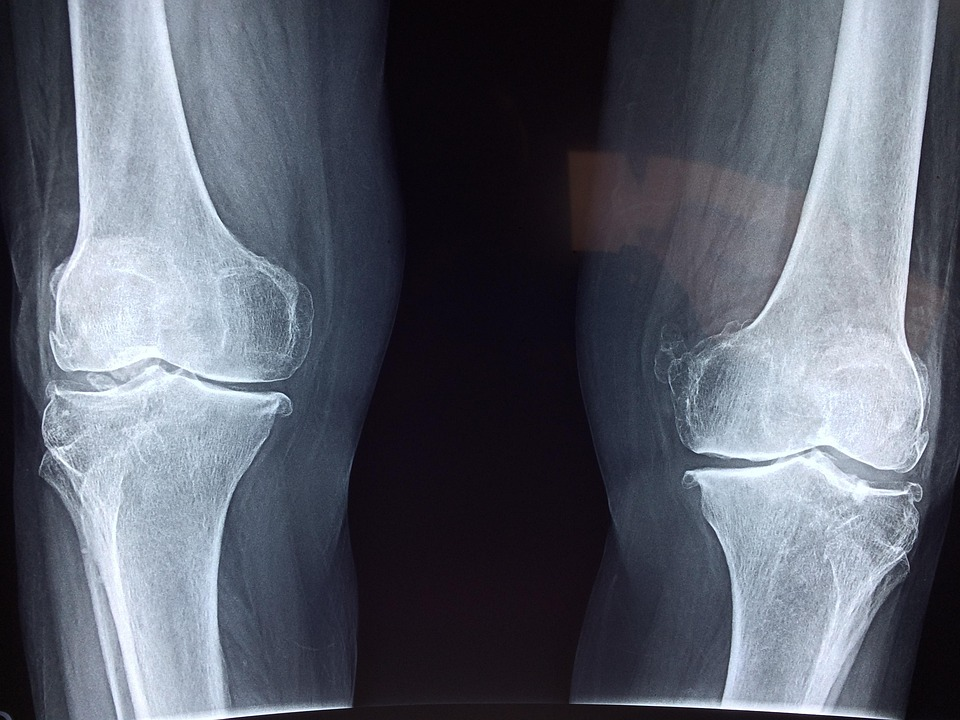

大脑健康与骨骼稳态密切相关。骨骼衰老的特征是骨形成不足和骨髓脂肪过多,但大脑是否参与了这一失衡过程尚不清楚。近日,中南大学附属湘雅医院骨科Hui Xie团队通过动物实验发现,衰老的大脑神经元(主要是海马和大脑皮层的神经元)会产生过量的名为WDFY1的蛋白,并通过细胞外囊泡(EVs)将其转移到骨骼中,从而导致骨脂失衡和骨质疏松。增加大脑中Wdfy1的表达会导致骨骼的过早衰老。相反,抑制全脑、海马或神经元中Wdfy1的功能,通过基因手段删除神经元中的Wdfy1基因,以及选择性地抑制神经元EV的释放,均可改善小鼠骨骼健康。在机制上,WDFY1与逆向运输复合物结合,促进组织蛋白酶D和过氧化物还原酶2从内体到高尔基体的再循环,从而抑制骨生成,并促进脂肪生成。相关论文于1月5日发表在《自然·衰老》(Nature aging)杂志。